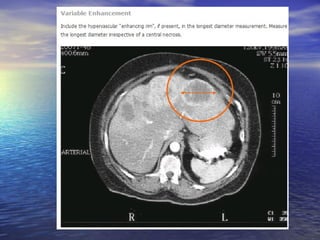

Diferença da avaliação em relação à fase do contraste

fase arterial                           Fase portal